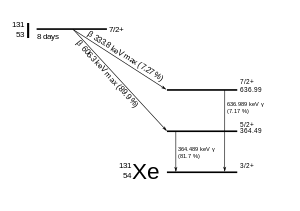

131I decays with a half-life of 8.02 days with beta minus and gamma emissions. This isotope of iodine has 78 neutrons in its nucleus, while the only stable nuclide, 127I, has 74. On decaying, 131I most often (89% of the time) expends its 971 keV of decay energy by transforming into stable xenon-131 in two steps, with gamma decay following rapidly after beta decay:

The primary emissions of 131I decay are thus electrons with a maximal energy of 606 keV (89% abundance, others 248–807 keV) and 364 keV gamma rays (81% abundance, others 723 keV).[14] Beta decay also produces an antineutrino, which carries off variable amounts of the beta decay energy. The electrons, due to their high mean energy (190 keV, with typical beta-decay spectra present) have a tissue penetration of 0.6 to 2 mm.[15]